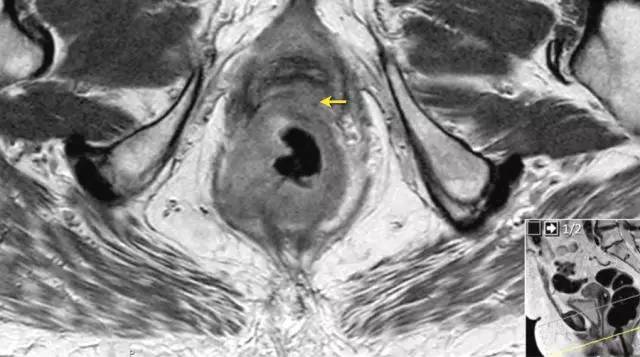

T4b 分期,侵入周围器官

T4 期肿瘤侵犯周围结构,如盆壁、阴道、前列腺、膀胱或精囊,这类局部晚期患者需要进行长程放化疗和广泛切除。

图 16 在矢状 T2W 图像上,直肠和阴道后壁之间有脂肪平面的损失。在轴向图像上,看到肿瘤的相对低的信号强度延伸到阴道的后壁(箭头)

以下 5 幅图例请连续观看:

图 17~21 肿瘤的低信号强度延伸到阴道的后壁(箭头)